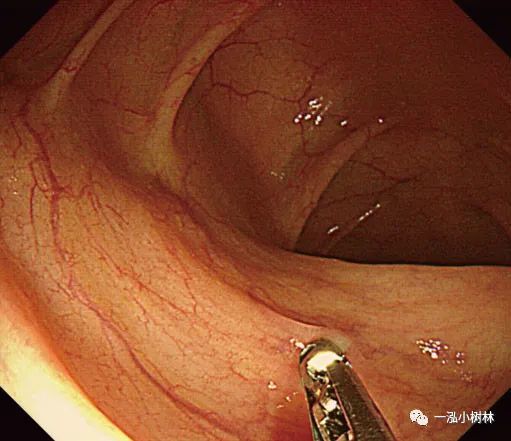

二、冷圈套息肉切除术

1.冷圈套息肉切除术(Cold snare polypectomy,CSP)是一种安全、有效的内镜下切除小息肉(小于10mm大小)的方法,但这一技术是理想的适应证是4~6mm大小的无蒂息肉。CSP与电切法相比,不存在潜在的穿孔风险。大小在10~13mm的圆形隆起息肉完全适合CSP。

图4a 小无蒂息肉的冷圈套息肉切除术

图4b 直肠5mm大小Is型无蒂腺瘤